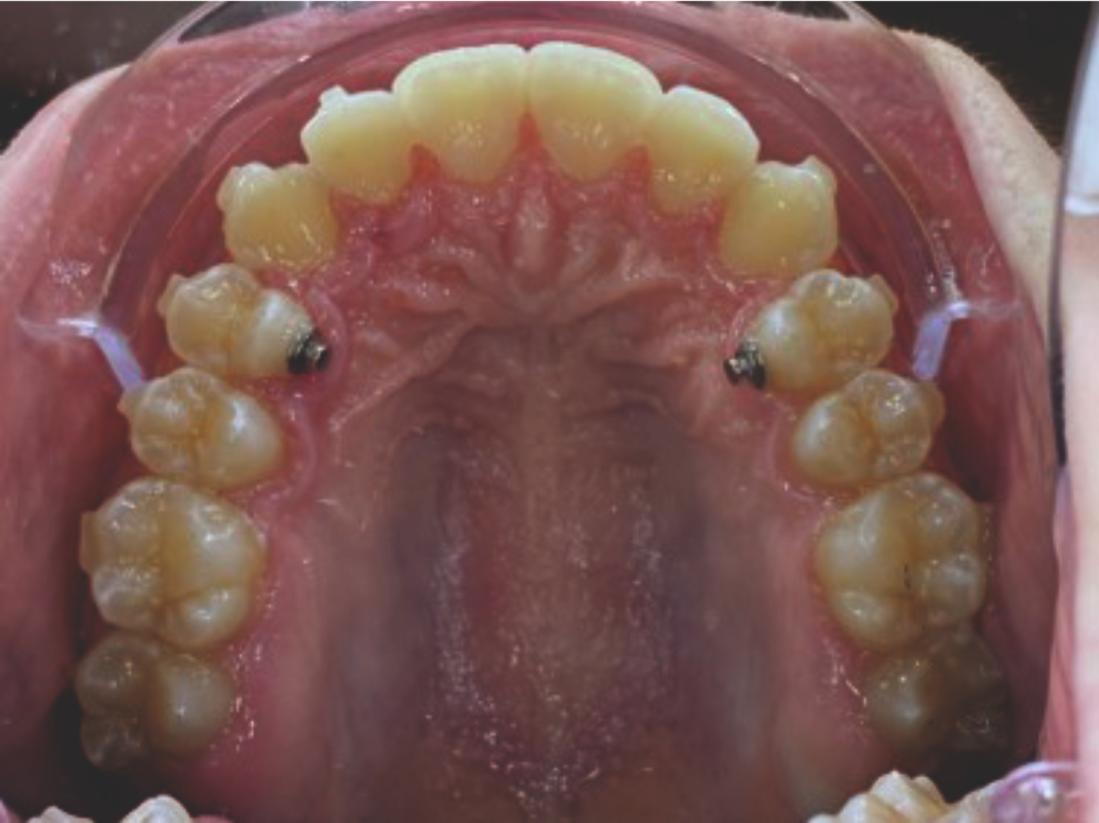

We approached the case by combining upper distalization using the A8 protocol with an asymmetric virtual jump. In this way, we solved the crowding without proinclining the incisors and improved the anteroposterior relationship through the use of elastics. In the lower arch, we carry out a development of the posterior sectors prior to the resolution of the crowding, in order to avoid roundtripping and excessive IPR of the incisors. To achieve an effective extrusion and distalization of 13, we combine the use of direct bonding button on vestibular of 13, with angelButton elastics mesial and distal to the canine. These mechanics help to ensure that the extrusion is real and that the aligner always remains adapted.

Treatment details

In the upper arch, the main goal will be to correct the Class II malocclusion by distalizing the upper posterior teeth in order to resolve crowding without proinclining the incisors. This movement will be accompanied by an asymmetric “bite jump” of 1 mm, which will help improve the skeletal Class II discrepancy, promoting mandibular projection, especially considering that the patient is still in the growth phase. Additionally, bilateral and symmetric expansion will be planned until a torque of 0° is achieved, allowing for proper transverse alignment and greater stability of the final result. Lingual button cutouts will be placed on teeth 14 and 24 to facilitate the required movements. To optimize control and retention, vertical mesial beveled attachments, as large as possible, will be placed on the premolars and molars, as well as on teeth 12 and 22, reinforcing the mechanics in the anterior sector. The inclination of the central incisors 11 and 21 will be corrected according to the visual reference provided in the clinical image. Furthermore, it will be necessary to center the upper midline by shifting it 0.5 mm to the left to achieve greater aesthetic symmetry. As for the lower arch, treatment will begin with a phase of expansion and derotation of the posterior teeth, which will set the stage for subsequent movements in the anterior sector. Once this goal is achieved, alignment of the teeth from canine to canine will proceed, aiming to minimize anterior interproximal reduction (IPR) and avoid unnecessary round- tripping movements of the incisors. Vestibular button cutouts will be made on teeth 36 and 46, while teeth 37 and 47 will have horizontal attachments that will serve as anchorage to ensure stability during treatment.